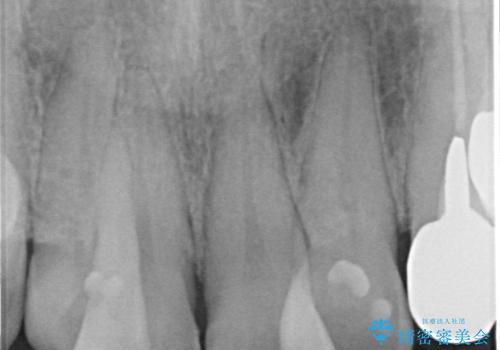

また、左上の犬歯の根の再治療も行いました。

- ジルコニアクラウンスタンダード・仮歯 13.2万円×6 左上3精密根管治療(リトリートメント)・ファイバーコア 12.1万円費用は治療当時の料金となります